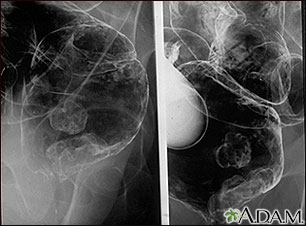

A barium enema in a patient with cancer of the rectum.